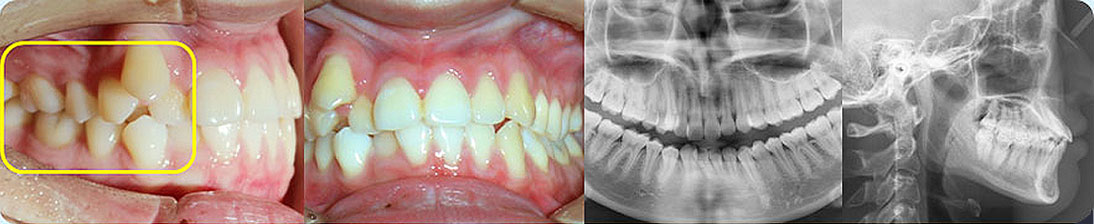

- 【診斷】

骨性I類,均角,安氏I類

上牙列重度擁擠,下牙列輕-中度擁擠

上中線右偏

13唇側(cè)錯(cuò)位

- 【治療方案】

拔除14,排齊上牙列

下頜尖牙適當(dāng)擴(kuò)弓,配合適量鄰面去釉,排齊下牙列

上頜左側(cè)配合適量鄰面去釉,調(diào)整中線

盡量調(diào)整后牙為尖窩咬合關(guān)系

矯治前后對(duì)比

蛻變周期:上頜16個(gè)月,矯治效率提升30%,下頜12個(gè)月,矯治效率提升20%